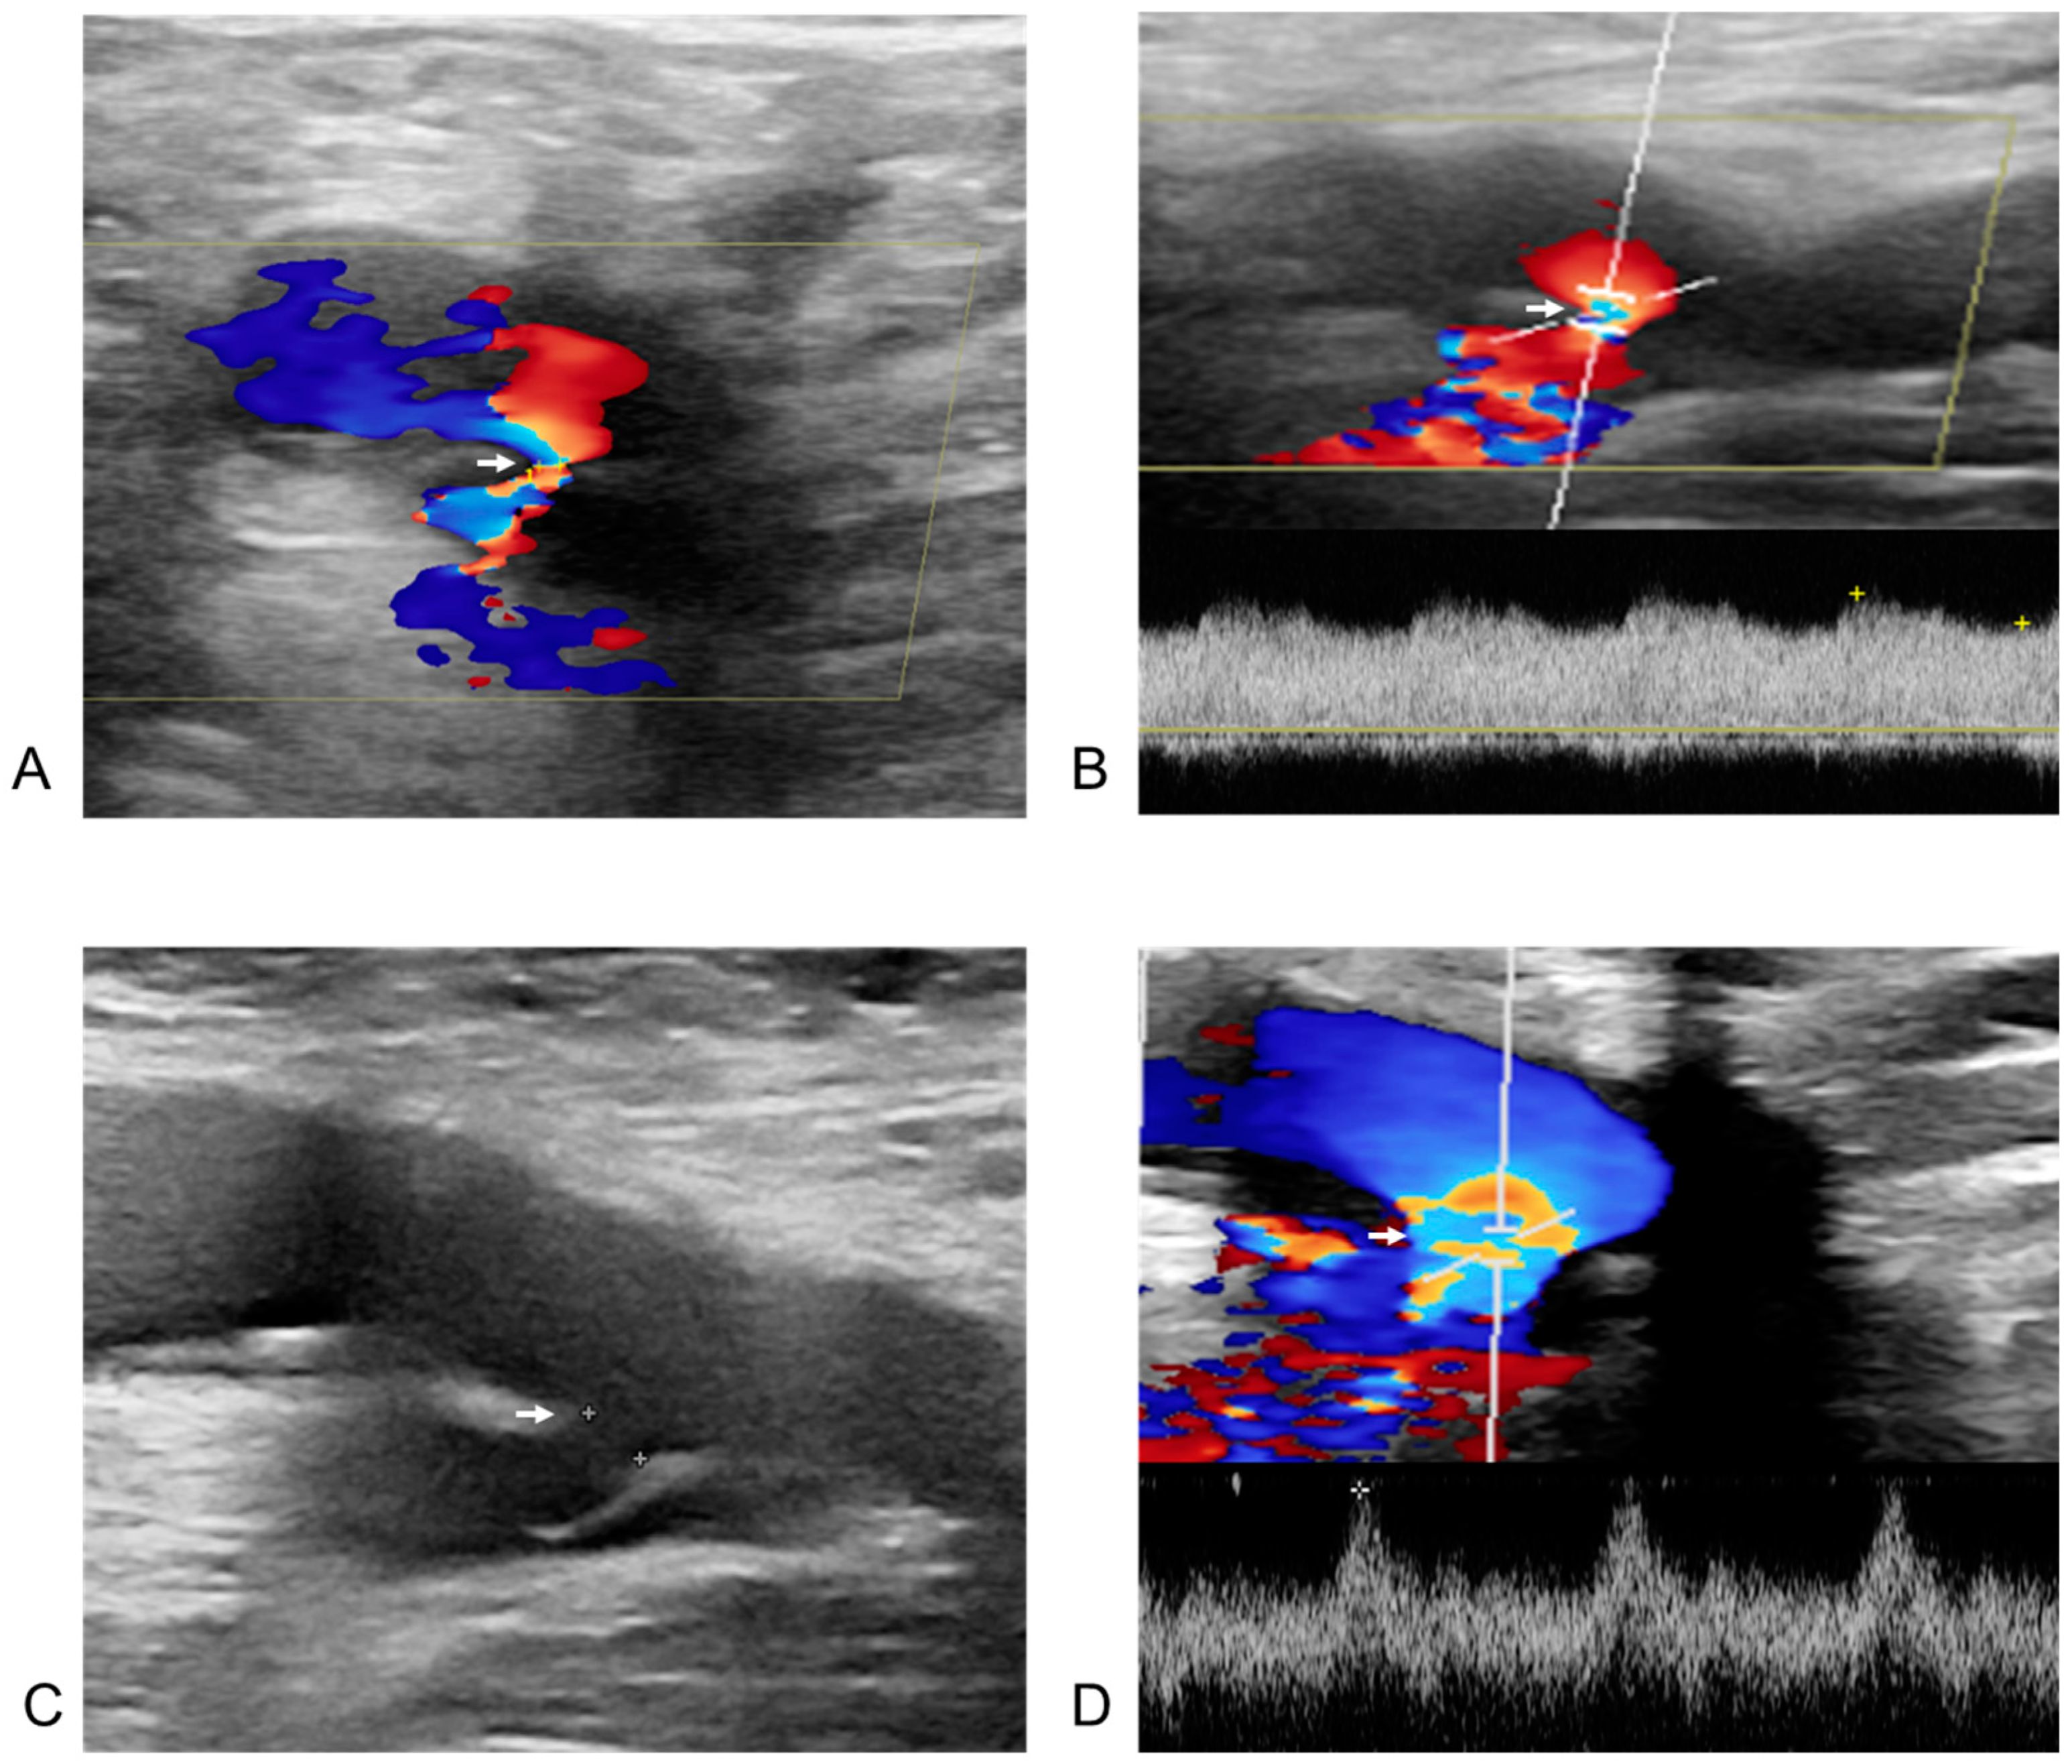

3.3. Incidence of Femoral Vascular Complications

3.4. Management of Femoral Vascular Complications